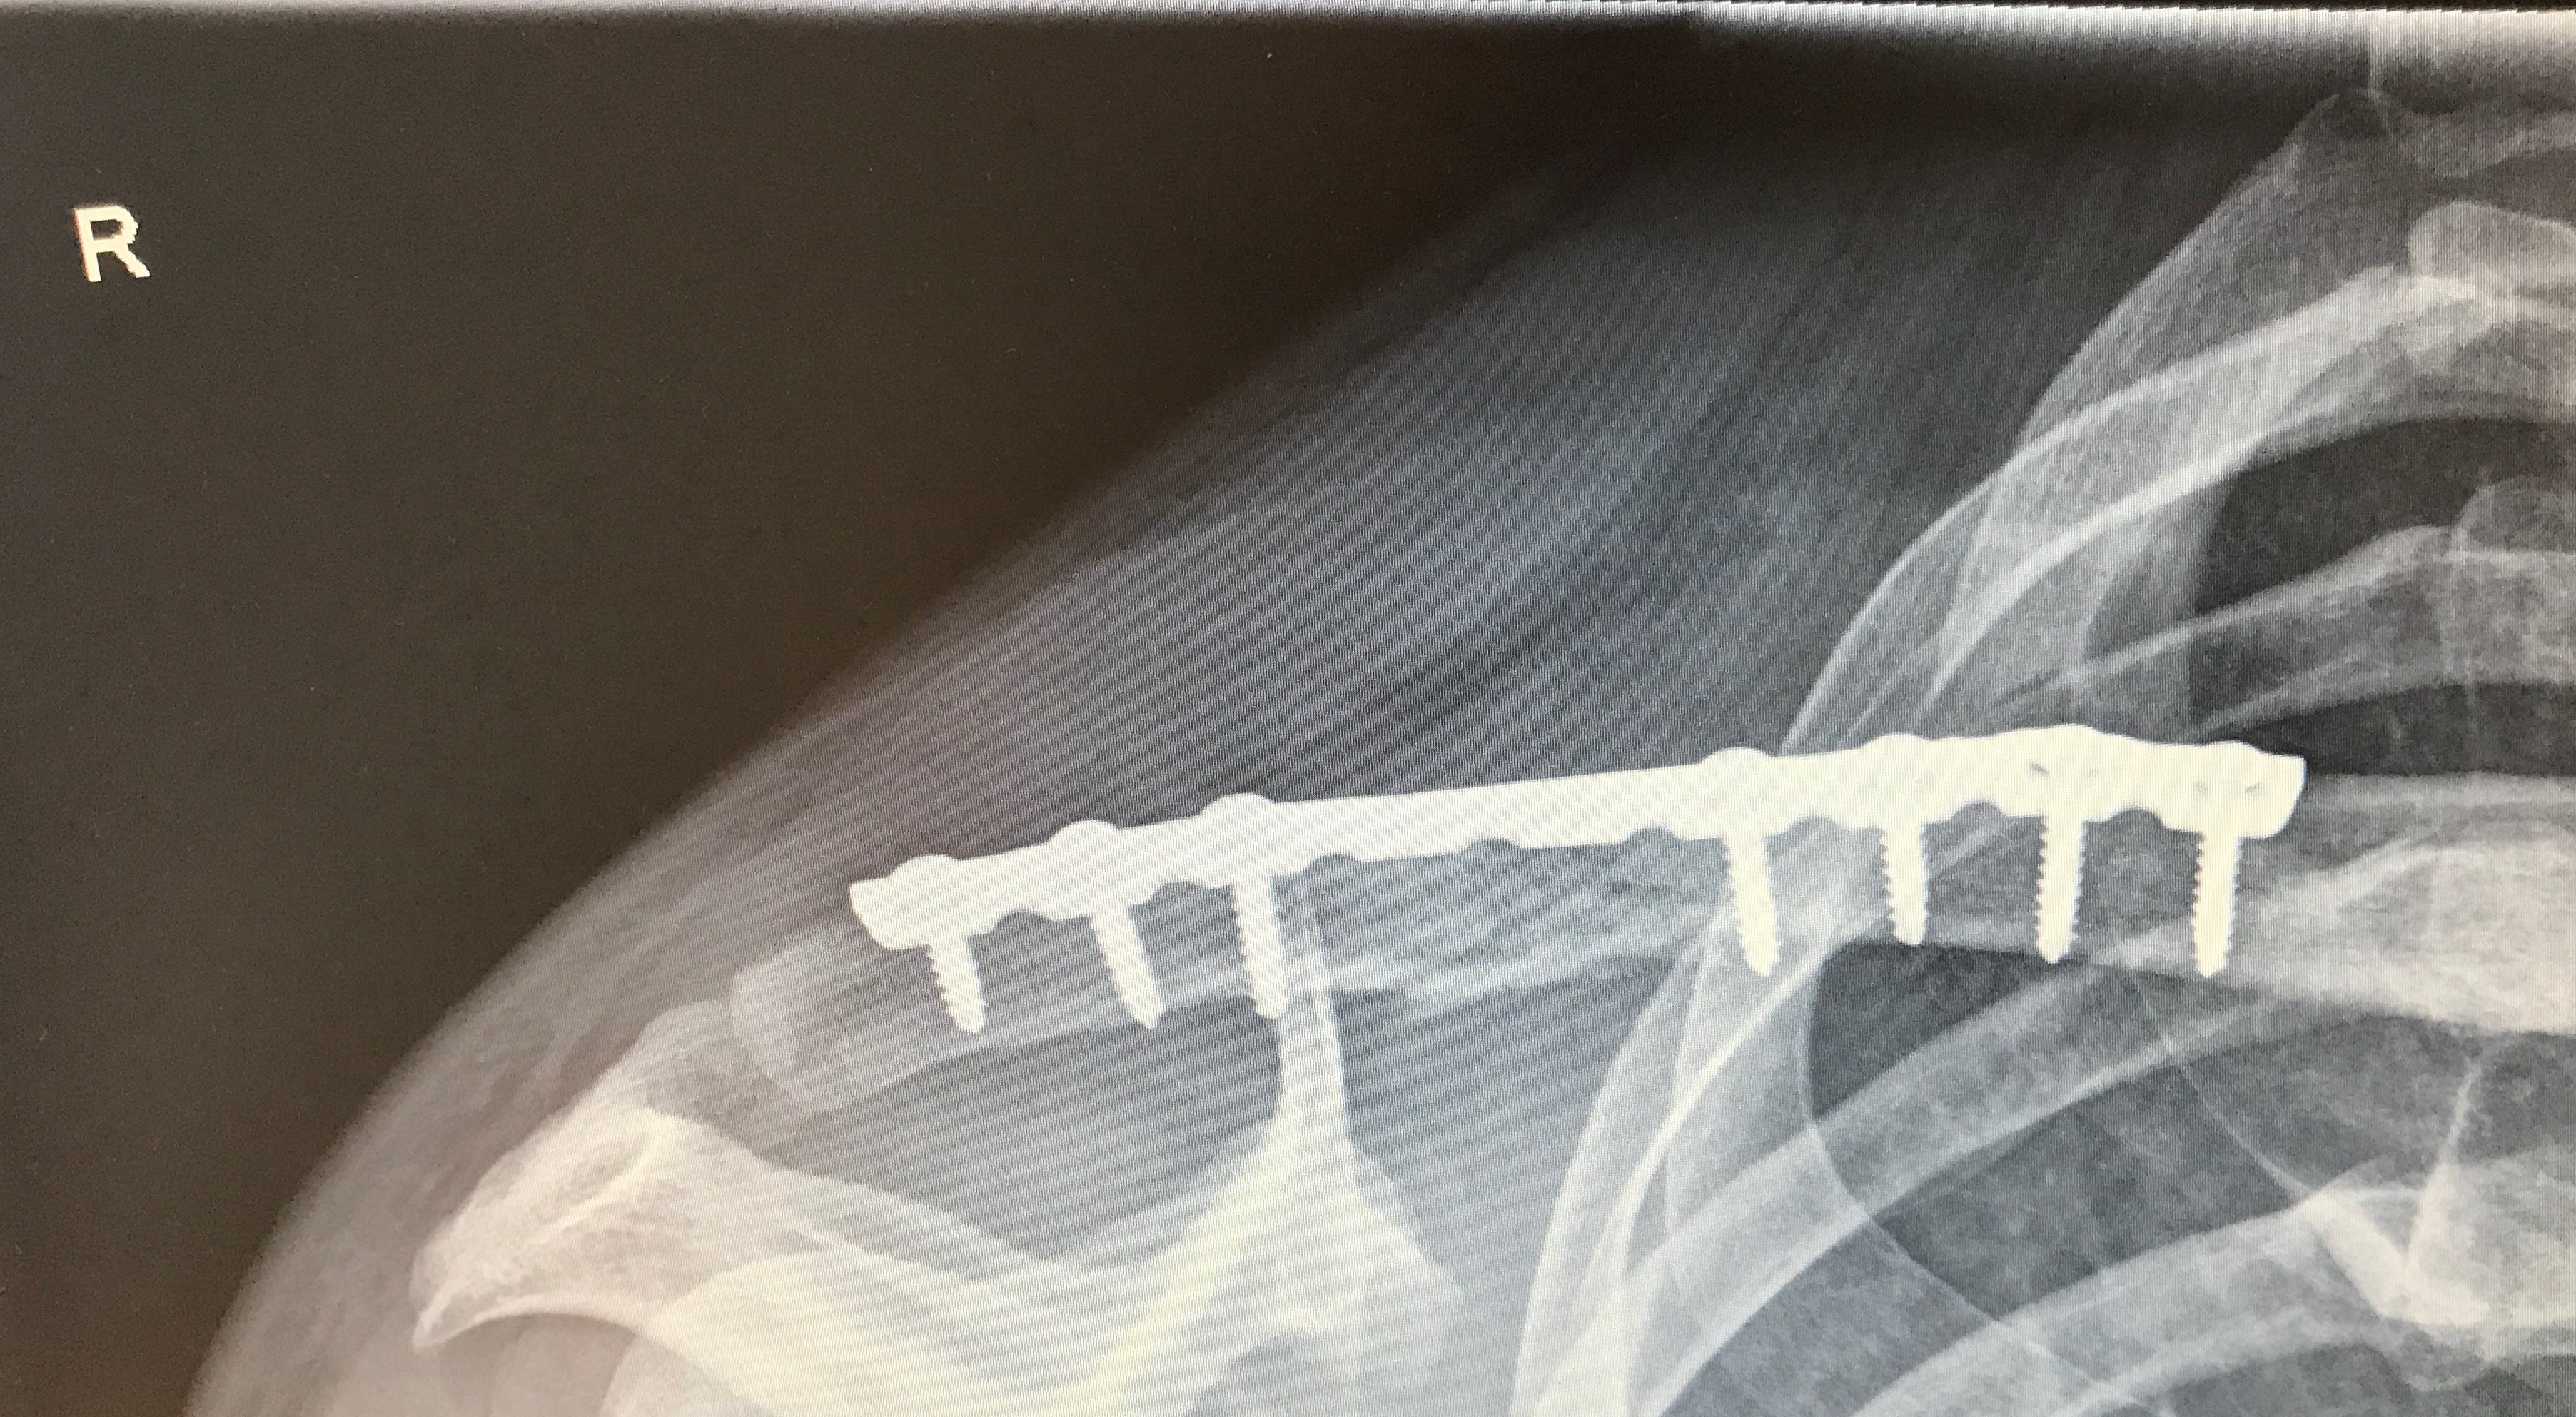

Bei der Titanplatten-Methode war mein Zeitablauf aber so ziemlich gleich. Du hast nur nach der OP halt die größere Wunde (bei mir ca. 13cm lang) und die entsprechende Wundversorgung zu beachten. Das heißt Pflaster immer entsprechend wechseln, nicht nass werden lassen. Das größte Risiko bei der Sache ist nämlich das Infektionsrisiko der Wunde. Auch das mitm nicht über die Schulter den Arm heben usw. war alles gleich.

Saß auch nach einem Wochenende wieder im Büro. Nach 4 Wochen hab ich mich ans Mopped-Schrauben gemacht nach glaub 6 war ich wieder am Joggen + leichtes Gewichte-Training. Nach 8 feuer frei. 10 Wochen nach dem Bruch hatte ich die nächste Veranstaltung und es ging ohne Einschränkungen (außer Kopf :? ).

Aber wenn die Nagel-Methode geht, würde ich sie wegen der kleineren Narbe bevorzugen.

SB2.jpg

SB1.jpg

Hast du deine Platte schon rausbekommen? Von den Bildern her könnte es mein Bruch sein, sogar die gleiche Seite :roll:

Mittig an dem Splitterbruch ist das Schlüsselbein inzwischen auch gut doppelt so dick wie an der gesunden anderen Seite, daher kann ich die Aussage das der Knochen nach einem Bruch stabiler ist gut nachvollziehen :lol: